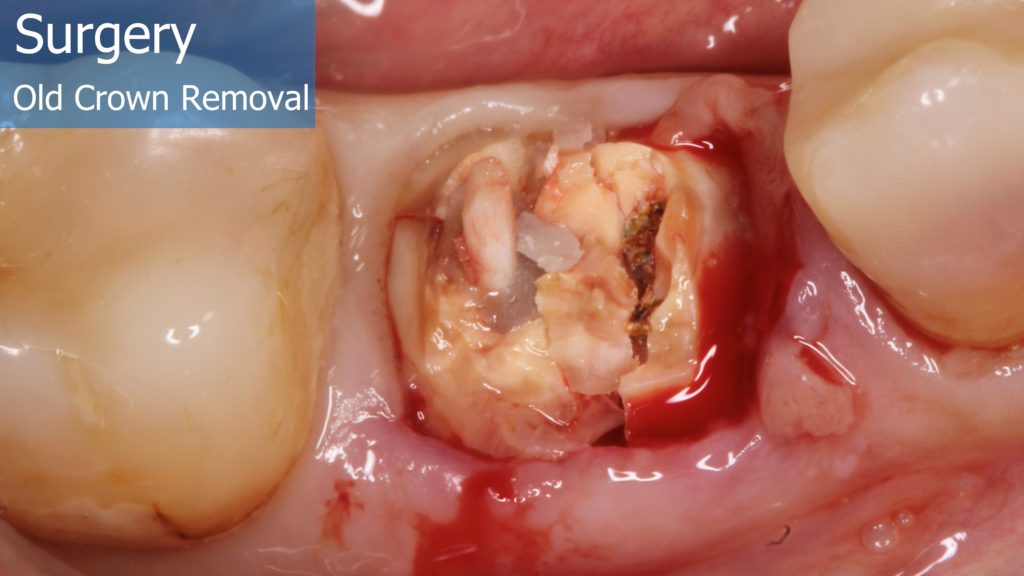

6-12 Months, Augma Bone Cement Academy, Bone Cement Expert, Clinical Cases, Clinical Indication, Clinician, Collagen Sponge/Plug, Coverage Used, Dental Notation, Images, Immediate Placement, Lower Left Molar, Media, Post-Op Period, Socket Grafting, Wound Dressing

Immediate Posterior Implant with Bone Graft

A healthy 36 year old woman comes to the clinic with pain and swelling in the area of the inferior left molars. In the intraoral observation, a vestibular fistula was identified, and the complementary exams confirmed a bone lesion caused by a root perforation (poorly executed false post) on the first lower left molar #36 (19). It was decided to do antibiotic therapy for a week and then the tooth extraction with immediate implant placement and bone graft. 4 months post-op the definitive zirconia/ceramic crown would be was made.